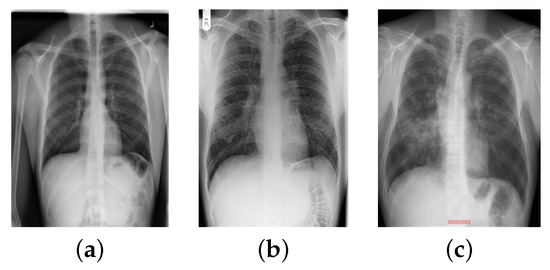

- Image Normalization: Different manufacturers of X-ray devices may provide different-looking X-ray images for the same patient. Overfitting to the device pixel distributions is quite a big problem in computer-aided diagnostic devices; therefore, it is standard practice to apply contrast normalization to minimize this problem. The general idea is to unify the distribution of pixels. This makes X-rays appear a little darker. This procedure generates a view that radiologists would not see in their standard workplace. Using the Reinhard and Macenko approaches, X-ray images were stain-normalized [43,48,49]. A reduction in the color discrepancies of X-ray images improves the classification accuracy of EfficientNet models.

- Data Augmentation: The normalized X-ray images were augmented before introduction into the EfficientNet model for training. The process of increasing the number of original images in a collection is known as data augmentation [38,50]. This strategy helps to eliminate the overfitting problem that arises when a model learns enough from the training data but cannot classify images of undetected X-rays. Table 3 illustrates the augmentation settings used on the stain-normalized X-ray images. In this study, the number of normal images was 1010, which is twice as many as the number of TB- and sarcoidosis-infected images. Therefore, the TB-infected images were augmented from 563 to 1126, and the sarcoidosis-infected images were increased from 231 to 462.